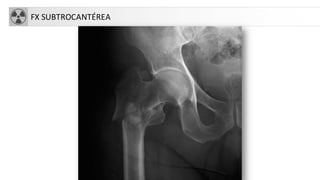

CLASIFICACIÓN

• Fracturascapitales: raras, asociadas a

luxación

• Fracturascervicales (intraarticulares)

1. subcapitales.

2. transcervicales

3. basicervicales

• 4. Fracturastrocantereas:

• cervicotrocantereas

• pertrocantereas(+frecuente)

• 5. Fracturassubtrocantereas

• Aisladas de trocanter mayor

• Aisladas de trocánter menor

FX SUBTROCANTÉREA